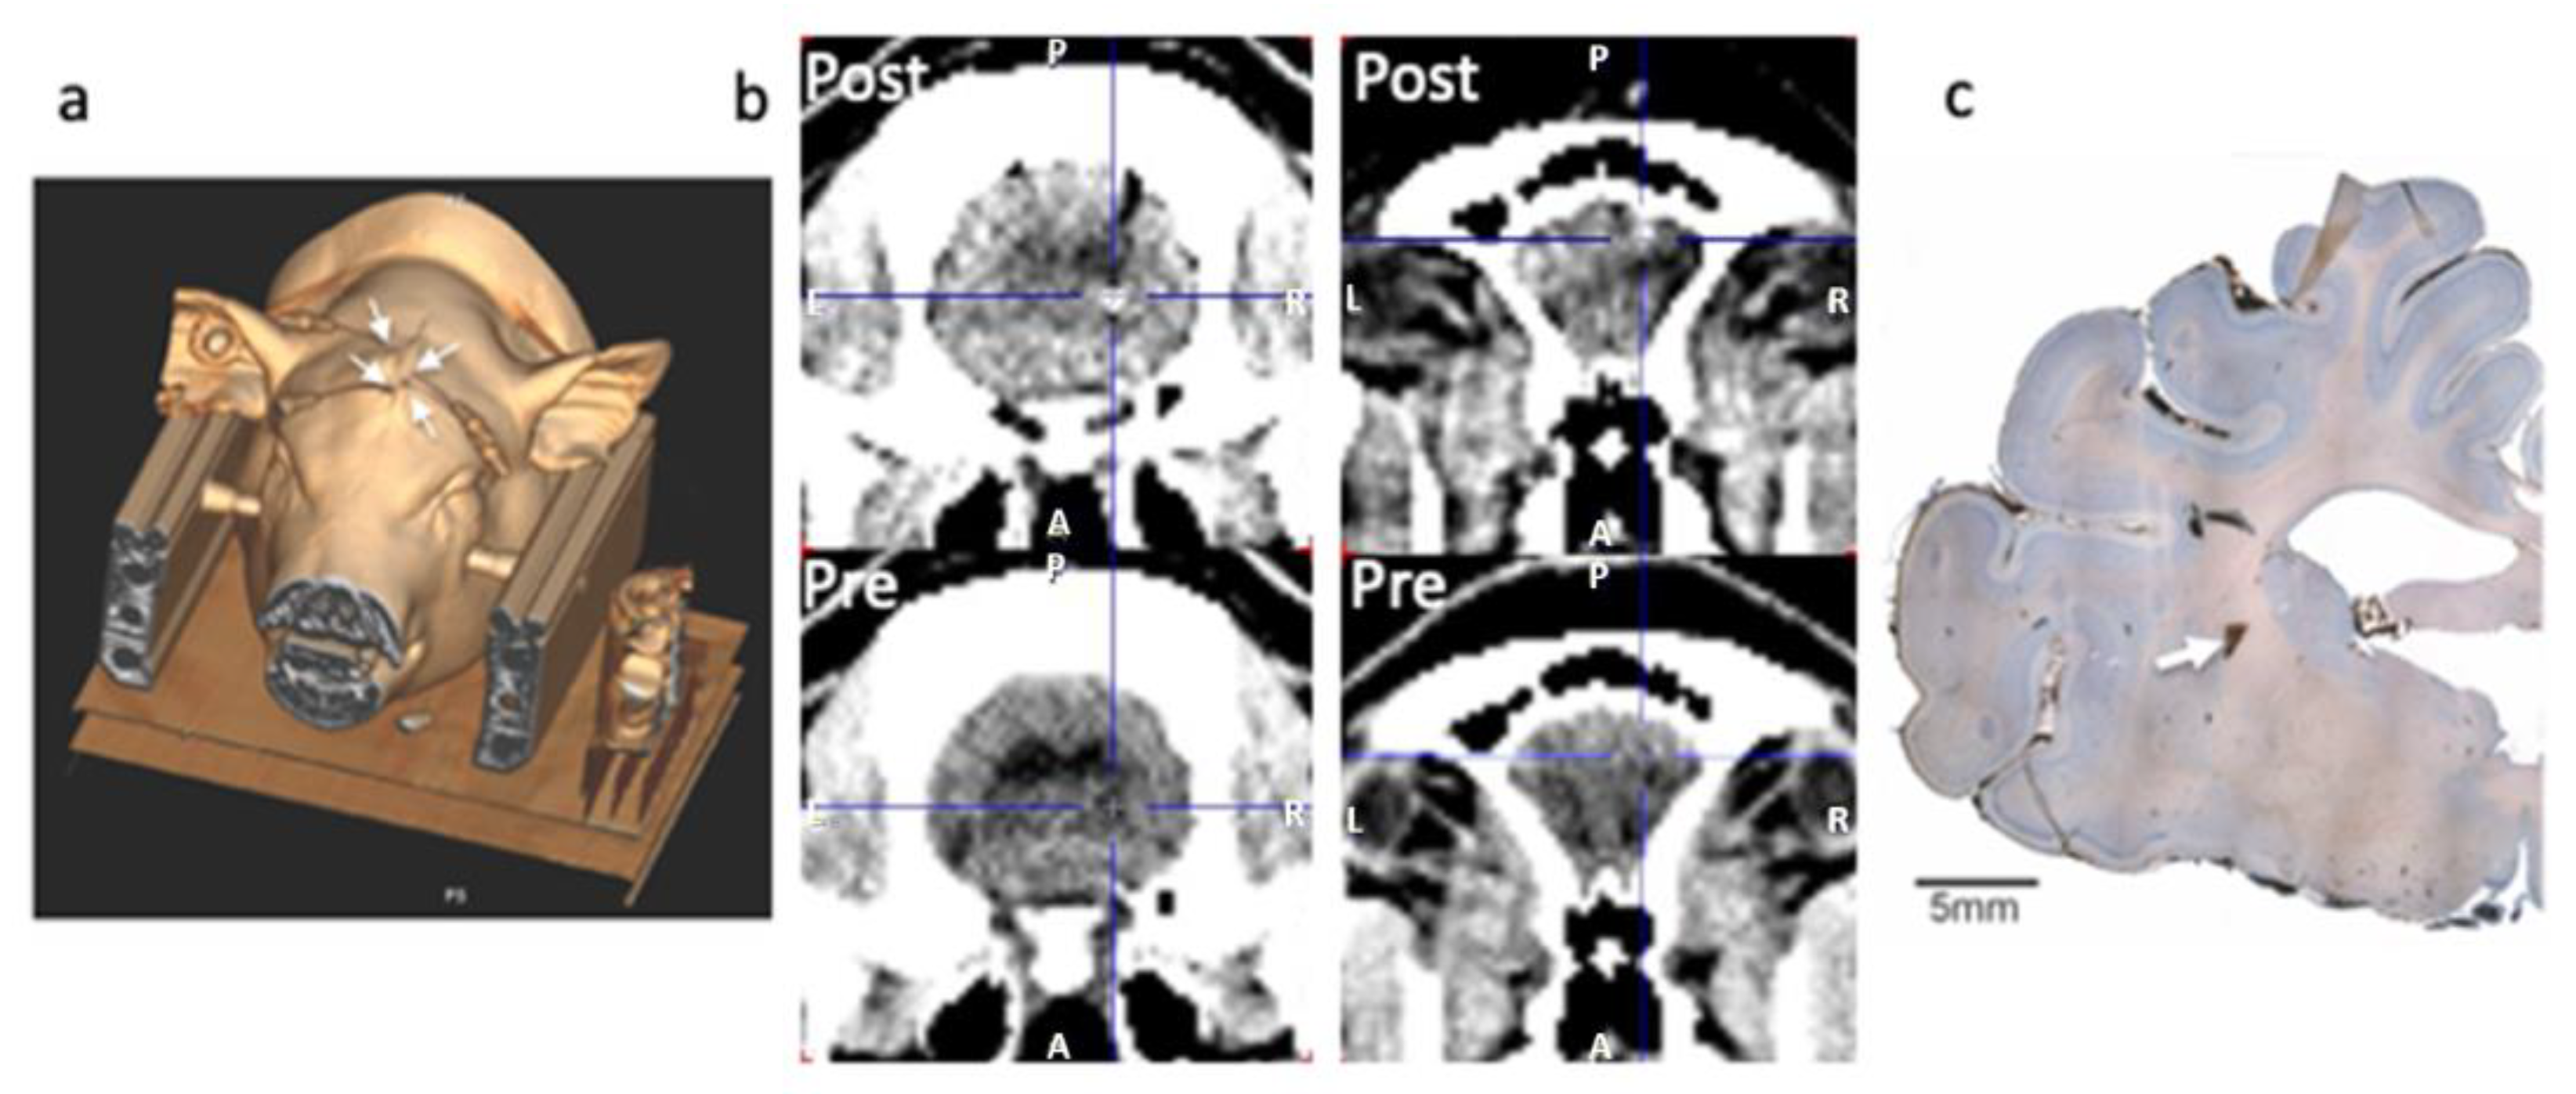

Minipigs were placed in a 3-point fixation head-holder designed for compatibility with PET and MRI [26], with two titanium tipped screws in the zygoma bone and a hard palate holder. Analgesia (1 mL bupivacaine 1%) was injected locally at the level of the zygoma screws and 8 mL was injected as infiltration analgesia at the surgical site. Prior to surgical intervention, buprenorphine (1 mL/3 micrograms) was administered IM. A midline incision was performed on top of the head, where local analgesia was applied, and the skull was exposed and dried before two small holes were drilled at the level of bregma and lambda to permit insertion of two temporary fiducial markers [27]. A high-resolution transmission CT scan (500 mAS, 120 kV, 1.0 mm 64 × 0.6 mm slice, 0.8 pitch) was obtained that allowed for sufficient identification of the skull, brain structures and fiducial markers in order to determine antero-posterior, lateral and dorso-ventral stereotaxic implant coordinates for the microdialysis probes (see Figure 1). The fiducial marker screws were removed and small holes were drilled above the regions of interest. The dura was gently punctured with a syringe needle tip to permit insertion of the probes into the brain parenchyma (Human CMA70 dialysis probes; membrane length: 1 cm; shaft: 10 cm). The probe shafts were cut to allow the membrane a 1 cm protrusion into the brain parenchyma and their descent to the pre-determined depth and location in striatum, thalamus and cortex, while the shafts had a tight fit in the burr holes and were firmly secured there with a surgical adhesive (Bioglue®). The skin was then loosely sutured around the probe shafts. Figure 1a shows a 3D reconstruction of the pig’s head in the scanner after implant of the dialysis probes (exit location of the probes shown by white arrows). This reconstruction was made from the CT scan obtained immediately prior to the PET studies for attenuation connection (50 mAS, 120 kV, 5.0 mm 24 × 1.2 mm slice, 0.8 pitch).

Figure 1.

Examples of methods used for validating the animal procedure and location of the microdialysis probes. Three-dimensional reconstruction of the animal in the head holder in the PET/CT gantry, obtained from the CT scan used for attenuation correction (a). The head of the animal is securely fixed in the stereotaxic headholder and the animal is advanced in the scanner in a prone position. The microdialysis probes can be seen exiting the closed midline incision (four white arrows) for connection to the pump and collecting vials on ice placed outside of the gantry for easy collection of the samples every 10 min. Two examples of probe location are shown in (b): the bottom row shows pre-implant CTs at the level of thalamus and frontal cortex. The top row shows the corresponding post-implant-pre-PET CTs with the gold tip target indicated by the cross hair as a white dot in the top image. An example of poor striatal location of the gold tip of the dialysis probe is shown in (c). In this image, the tip location (white arrow) appears to be in the internal capsule, between caudate and putamen. This image, covering an entire hemisphere of the pig brain, is a combination of the 40–50 microphotographs merged in Photoshop software.

The position of the gold thread in the tip of the microdialysis catheter can be visualised on a CT scan. Verification of the probe location in the brain was performed initially in vivo by comparison of the initial high-resolution CT (pre-implant) with the low-resolution CT scan performed immediately prior to the PET scan for attenuation correction of the PET data. The anatomical location was confirmed using pig brain atlases [32,33,34]. An example of pre- and post-CT comparison is shown in Figure 1b.

Upon removal of the probes from the brain, clotted blood was noticed on the tip of two of the probes and the data from these probes were negative throughout the sampling day. The tip of 3 more probes appeared slightly bent/cracked, suggesting damage at insertion or during removal from the brain. If the HPLC data suggested that the probes were damaged at insertion (poor recovery or no measurement), data from these probes were excluded. The entire datasets from 2 animals (1 nisoxetine, 1 low dose amphetamine) were lost due to an unnoticed freezer failure. The data from 2 cortical probes were excluded as we could not confirm the location and, as a whole, the cortical probes provided the most variable data and were located as much in white matter as in grey matter. The tip of one striatal probe was located in white matter (internal capsule) and was excluded (Figure 1c). The other probes were located mostly in cortical or thalamic grey matter (Figure 1b) but the size of the dialysis membrane (10 mm), while permitting a wide sampling area, made it difficult to remain localised completely within one grey matter region, likely increasing sampling variability. We therefore lost the data from a total of 16 probes and considered the results from the remaining 32 probes.